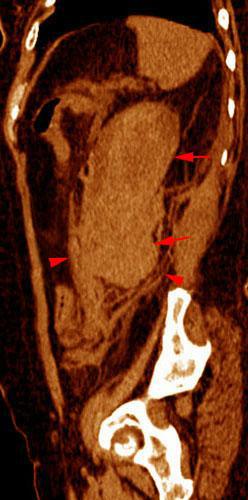

Hematoma subcapsular y perirrenal

VR seccional. Visión sagital izquierda. Exploración no contrastada que muestra un hematoma subcapsular protuyendo en el espacio perirrenal (flechas). Obsérvese la infiltración hemática de la cápsula de Gerota (puntas de flecha)